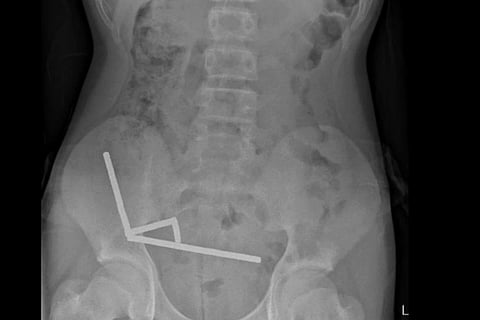

Abdominal X-ray with four linear chains of magnets in the right lower quadrant.New Zealand Medical Journal

Teen Loses Part of Bowel After Swallowing 80+ Magnets

Once inside his digestive tract, the magnets pulled sections of his bowel toward each other, causing severe internal damage